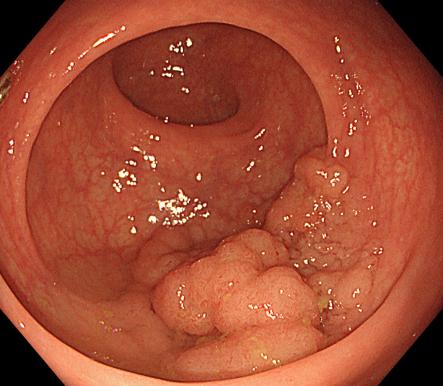

0d0b80a96701483cbcbf8b67351feac3.Jpeg8f7177645651428ca3a0f3c87dfd559d.Jpeg

直腸側(cè)向發(fā)育性腫瘤      內(nèi)鏡下黏膜下剝離術(shù)后創(chuàng)面

內(nèi)鏡下黏膜剝離術(shù)(ESD):治療巨大平坦息肉,早期癌及癌前病變,黏膜下腫瘤等。